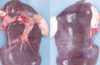

Generalised peritonitis